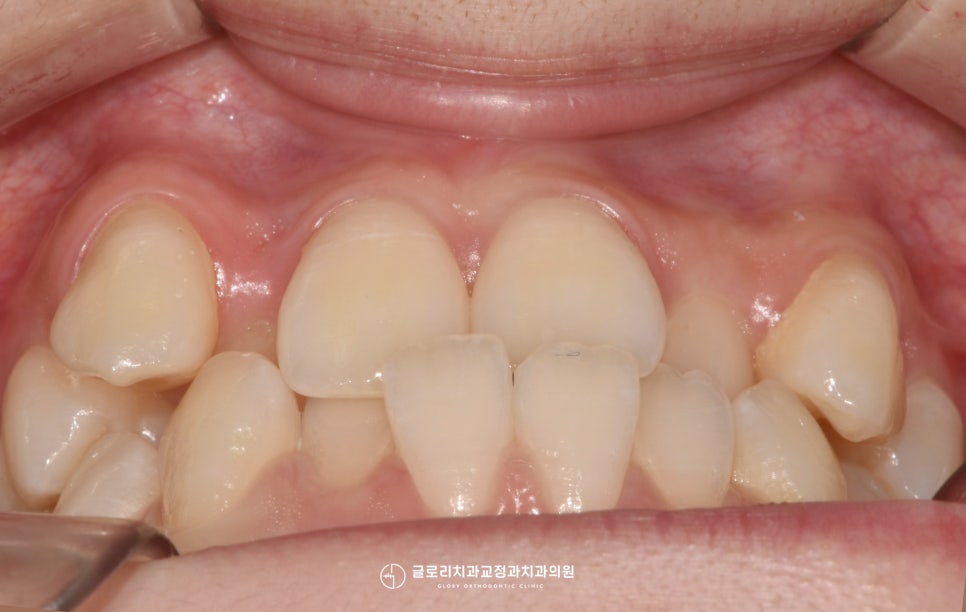

정확한 진단을 위해 구내를 먼저

환자께서 말씀하셨듯이 심한 덧니가

바로 눈에 띄는데요.

양쪽 위 송곳니가 위쪽으로 솟아

제 위치가 아닌 곳에서 자리 잡아

더욱더 도드라져 보입니다.

게다가 또 다른 문제점 또한

찾아볼 수 있었는데요.

앞니쪽을 보시면 어색한 듯 물려있는

형태를 관찰하실 수 있는데요.

보통 윗니가 아랫니를 덮는 자연스러운

피개 방식으로 되어있어야 되지만,

이 경우에는 거꾸로 물리는 반대교합을

나타내고 있었습니다.